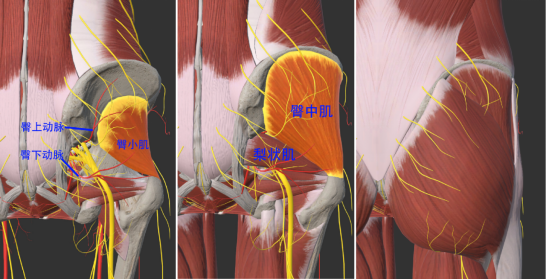

二、解剖基础

骶丛:由腰骶干(L4、L5)以及全部骶神经和尾神经的前支组成,从坐骨大孔穿出。支配盆壁、臀部、会阴、股后部、小腿以及足肌肉和皮肤。分支有:臀上神经(支配臀小肌和臀中肌)、臀下神经(支配臀大肌)、阴部神经、股后皮神经、坐骨神经、股方肌神经、闭孔内肌神经等。